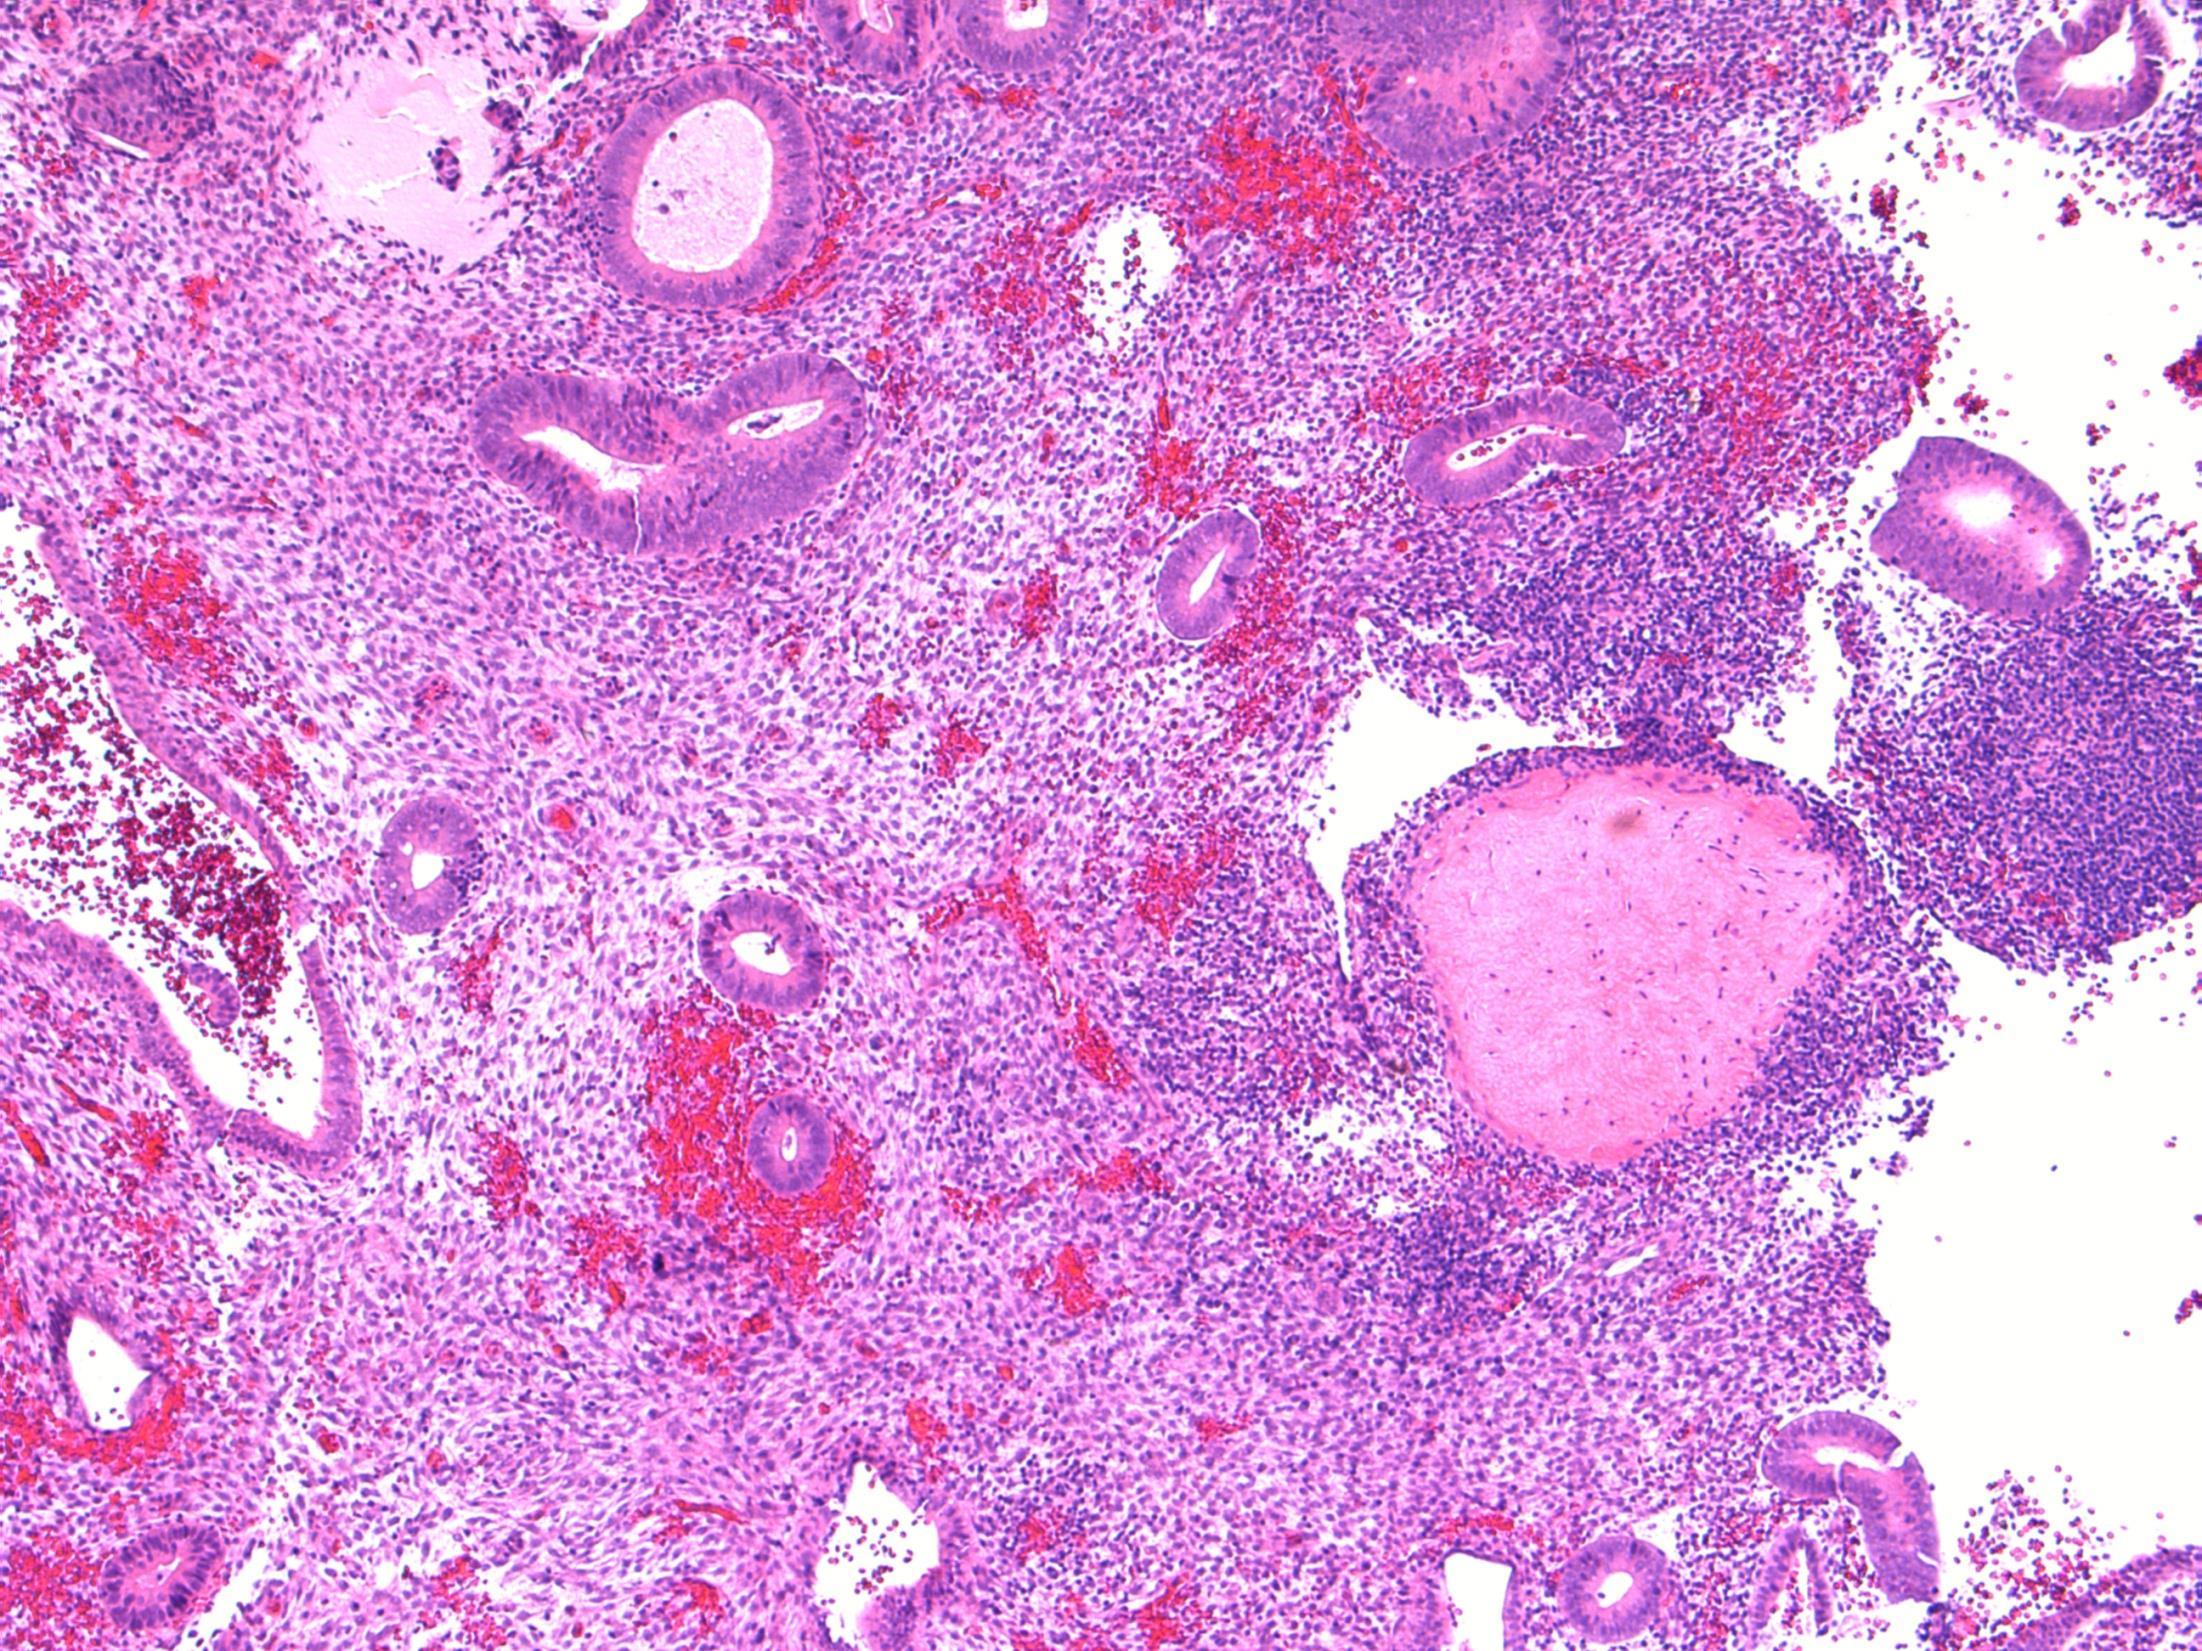

Description: Fragments of endometrial tissue containing proliferative phase glands. In addition there are well-circumscribed hyalinised nodules containing epithelioid trophoblastic cells. No evidence of malignancy.

Diagnosis: Proliferative endometrium with old placental site / placental site nodule

Differential Diagnosis: Placental site trophoblastic tumour (larger, not well circumscribed, less hyalinization, mitotically active, weak staining for PLAP)

Plan: IHC: Trophoblast is AE1/3, p63, PLAP, inhibin +ve, hcg -ve

Correlate with history of a previous pregnancy.

Comments:

Previous gestation that fails to involute. May be identified many years after pregnancy. Often an incidental finding on endometrial biopsies.